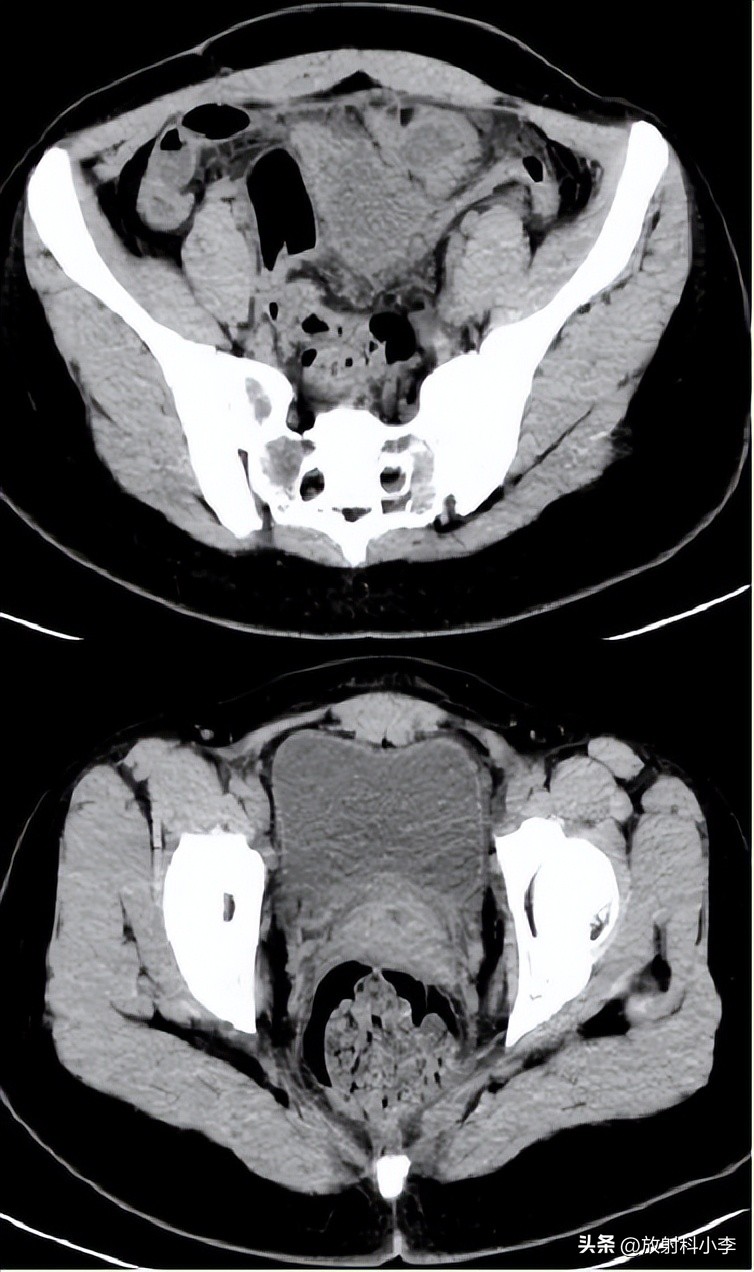

case 1. F,42Y,突发右下腹痛半天

CT:右侧附件区见一混杂密度肿块,可见脂肪密度,肿块壁增厚,与子宫之间的连接结构增粗、稍扭曲,密度不均匀。考虑右卵巢畸胎瘤蒂扭转。

case 2. F,84Y

3年前的CT平扫示:左侧附件区肿块,主要呈实性,平扫密度较高,伴出血;3年后CT示:左侧附件区肿块较3年前明显增大,呈囊实性,实性成分为主,增强强化轻或无,瘤周见条带影/团块影与子宫相连。